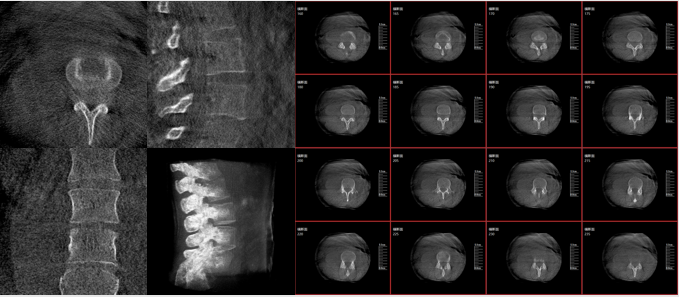

隨著醫學影像技術的發展和對精準手術需求的提升,傳統C臂的二維影像逐漸不能滿足手術所需的信息要求,這時,術中三維C臂應運而生。術中三維C臂就是將傳統二維與“類CT模式”相結合的升級版C臂,能在術中快速地生成橫斷面、矢狀面、冠狀面斷層圖像和三維立體圖像。

術中三維C臂通過不同方位的斷層圖像,能夠更清晰、完整地顯示椎體及其附件的解剖學結果,直觀地分析病變與周圍組織的立體空間關系,三維斷層成像能夠使手術模擬和手術方案的制定更加準確。

而三維影像的MPR圖像組可以通過不同平面的切分,使成像區內更豐富的信息得以呈現。尤其是二維影像無法涉及的橫斷面,提供了另一個空間維度的信息量。

術中三維C臂影像

作為使用者,醫生在手術中雖然有術前的影像作為判定依據,但每一臺手術都具有獨特性,需要術中三維C臂影像提供的實時信息,作為術中診療操作的基礎。

術中三維C臂影像帶來的更加豐富的信息,可以作為醫生手術執行的判斷基礎,以及手術操作后實時的影像判斷依據,從而保障手術效果。

在既往的手術中可能會出現這樣的情況:術后在影像科CT檢查中發現某個手術效果需要調整,這時往往需要返臺、翻修等才能解決。而術中三維C臂提供的術中三維影像功能可以將這一步驟合并至手術流程中,有效地降低醫患雙方的風險,為手術保駕護航。

近年來,機器人導航設備在臨床的應用越來越廣泛,而術中三維C臂影像是機器人導航系統手術執行的基礎,具有地圖定位和效果檢驗的雙重作用,使手術執行更加準確,手術效果驗證更有保障。